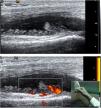

Como hallazgo diferencial, la afección articular de las SpA presenta algunas características propias como calcificaciones u osificaciones en las zonas de inserción de la cápsula articular, pero este hallazgo no es constante y no está validado todavía. En las SpA, dado que en general son formas oligoarticulares y asimétricas, no hay índices articulares de exploración estandarizada preestablecidos, sólo en la forma poliarticular de la artritis psoriásica serían aplicables los tradicionales índices de exploración incluidos en el DAS 28 o el índice de 42 articulaciones, similar a los índices de la artritis reumatoide. Los índices reducidos que se aplican en la artritis reumatoide no han sido validados en las SpA ni en la artritis psoriásica. En cuanto a la cuantificación de la actividad inflamatoria por Doppler, se usan las mismas escalas de valoración que en otros tipos de sinovitis inflamatorias; la más usada es la escala semicuantitativa de 0 a 3 (grado 0, ausencia de señal Doppler; grado 1, menos de tres vasos aislados en el tejido sinovial; grado 2, vasos confluentes o más de tres vasos y menos del 50% de la sinovial con señal Doppler; grado 3, más del 50% de la sinovial visible en la ventana Doppler con señal Doppler) (fig. 1).

Ecografía de entesis aquílea. A) Corte longitudinal en el que se aprecia señal Doppler en bursa preaquílea y en la entesis, tanto en el tendón como en la zona de erosión. B) Erosión en calcáneo en plano longitudinal. C) Erosión en calcáneo en plano transversal. D) Corte longitudinal, entesofito en formación, imagen hiperecoica paralela a las fibras del tendón, crecimiento óseo cortical que invade la entesis en su zona distal, alteración hipoecoica de la estructura con pérdida localizada del patrón fibrilar.